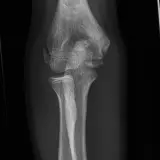

Over 2,100 interactive radiology cases, curated by radiologists for your level of training. Scroll, window, and view cases full screen — just like on PACS. Click linked findings in each writeup to jump straight to them on the image. Cases include sample reports, a focused discussion section, original illustrations, and videos.

完全交互式病例,配备您在 PACS 上期待的各项工具——滚动、调窗、缩放、平移、测量、ROI 和全屏模式。

丰富的标注直接在病例图像上突出关键发现。点击病例讲解中的关联发现,即可跳转至其在扫描上的精确位置。

交互式病例

像在工作站 PAC 上一样滚动、平移、调窗和缩放

通过标注的影像发现与示意图高效学习